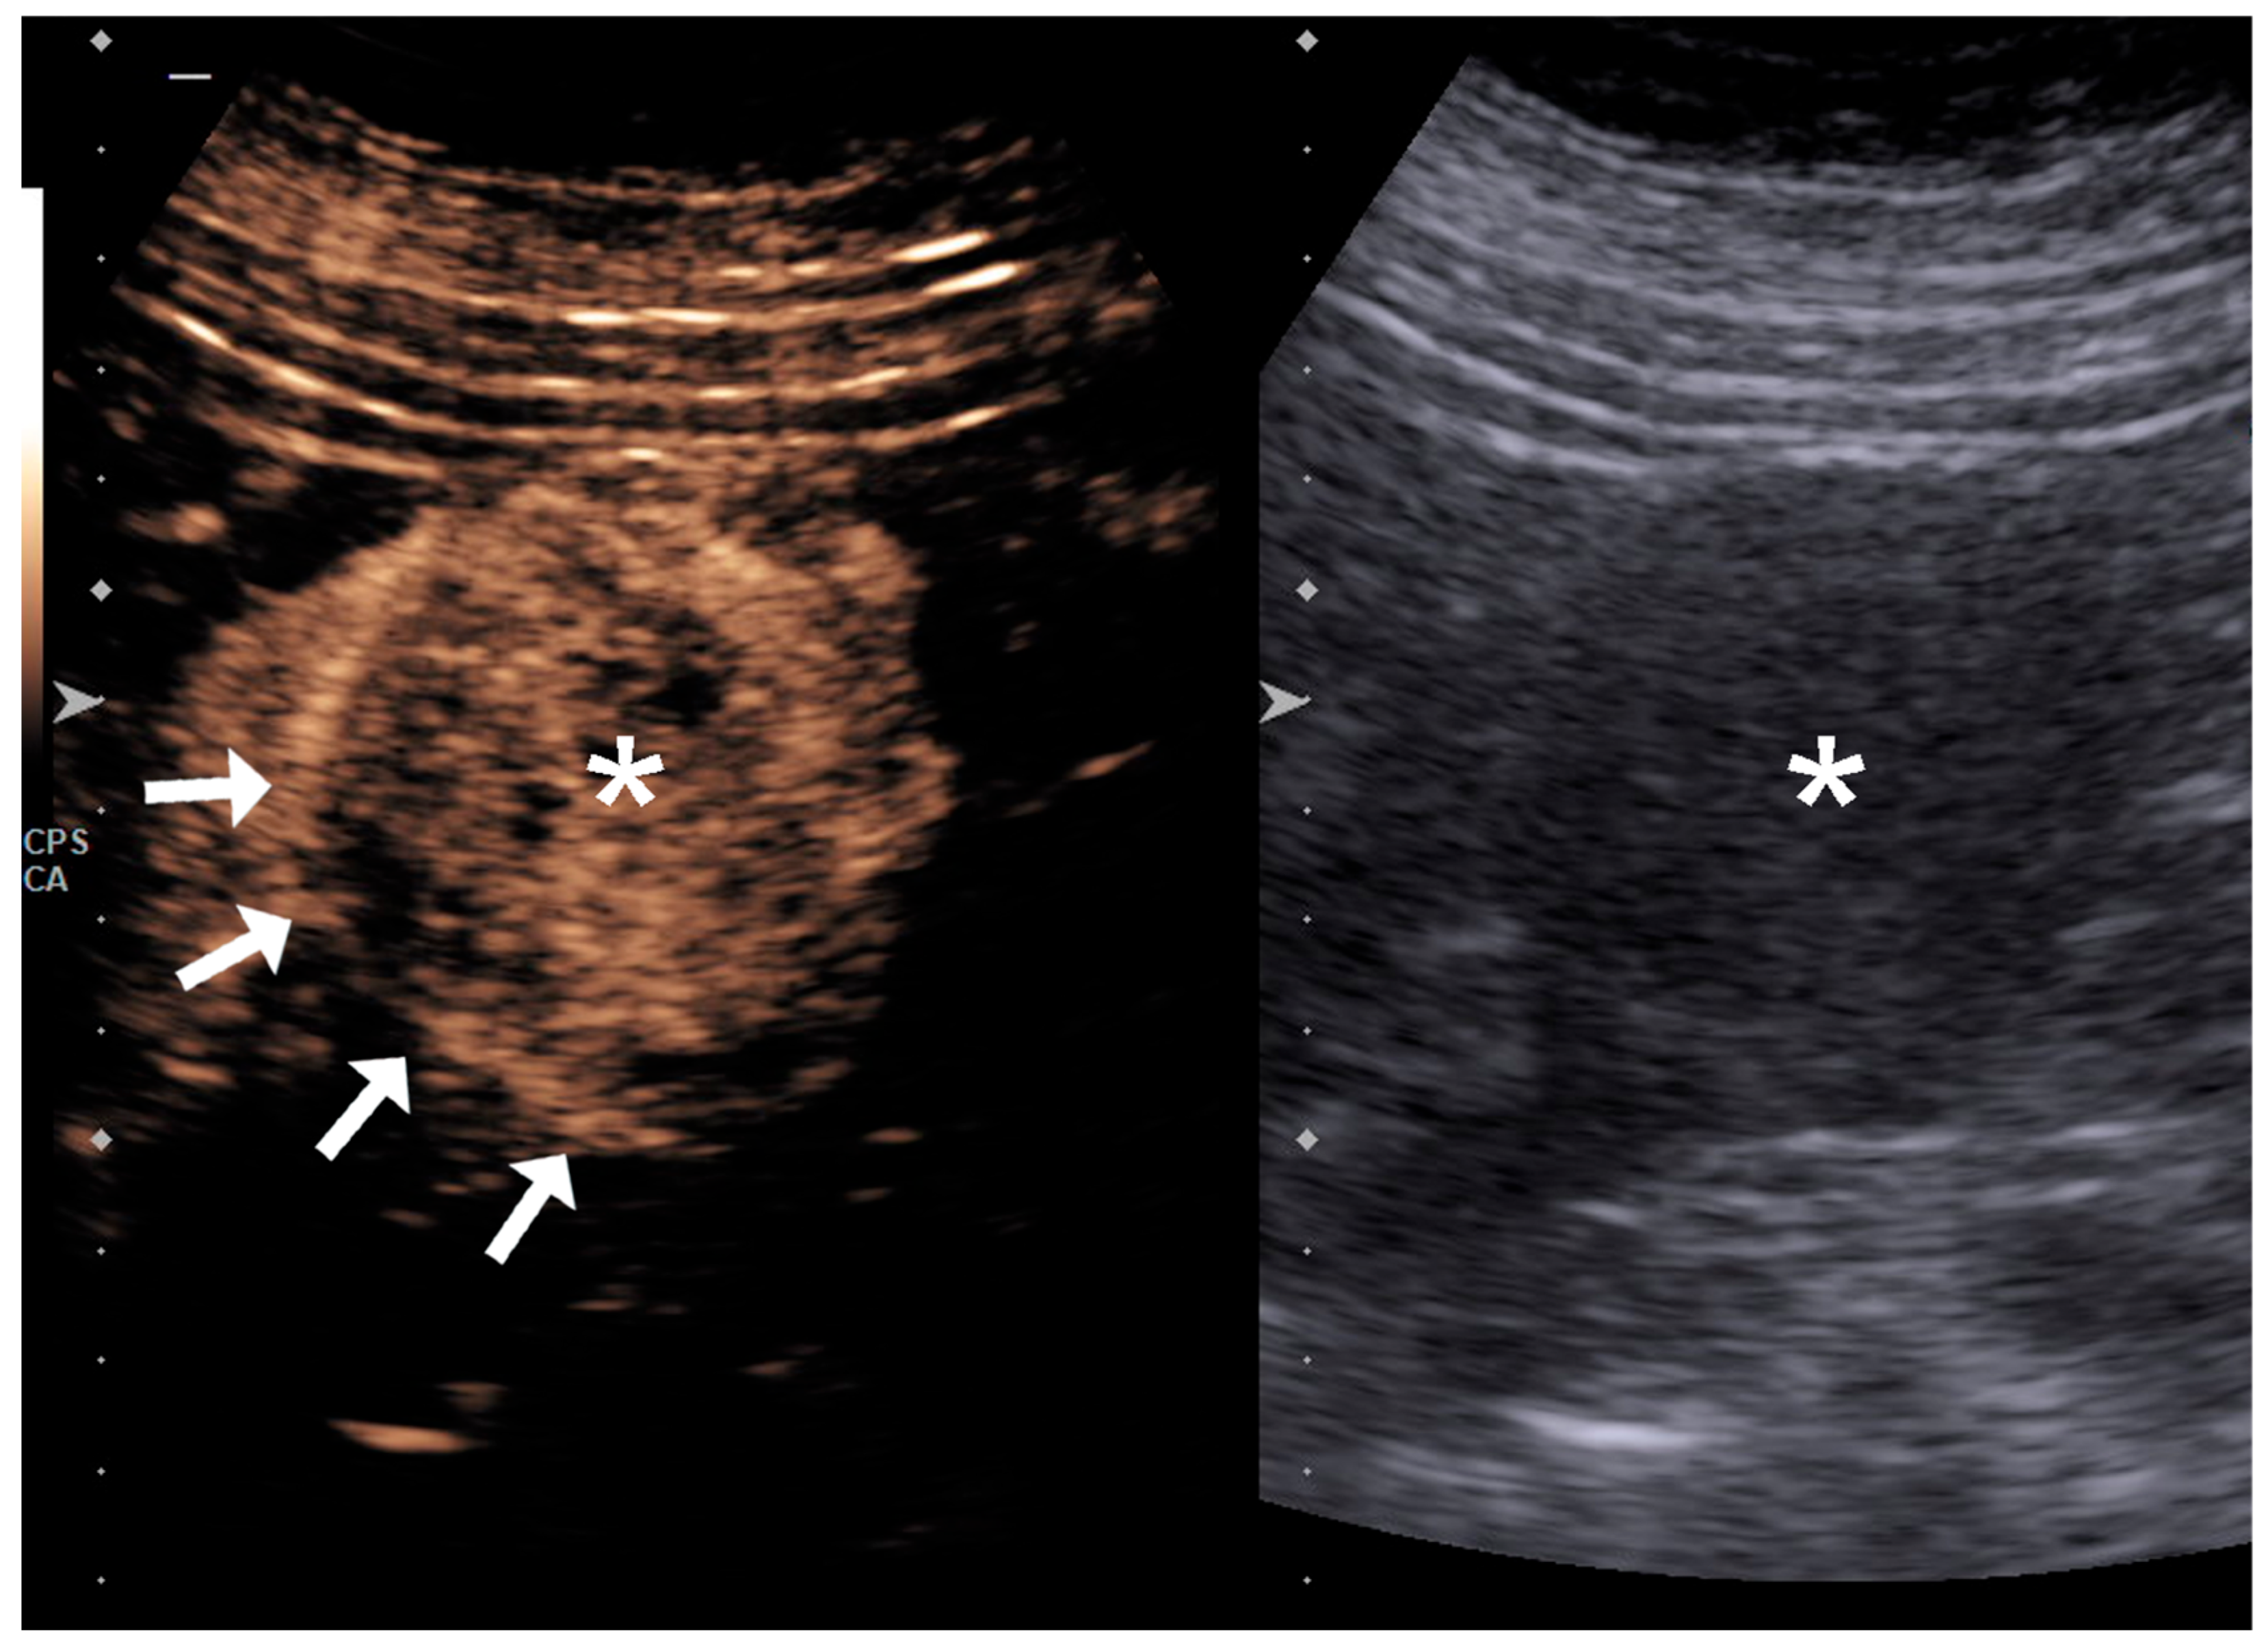

2.2. Image Acquisition and Analysis

4.1. Qualitative Evaluation